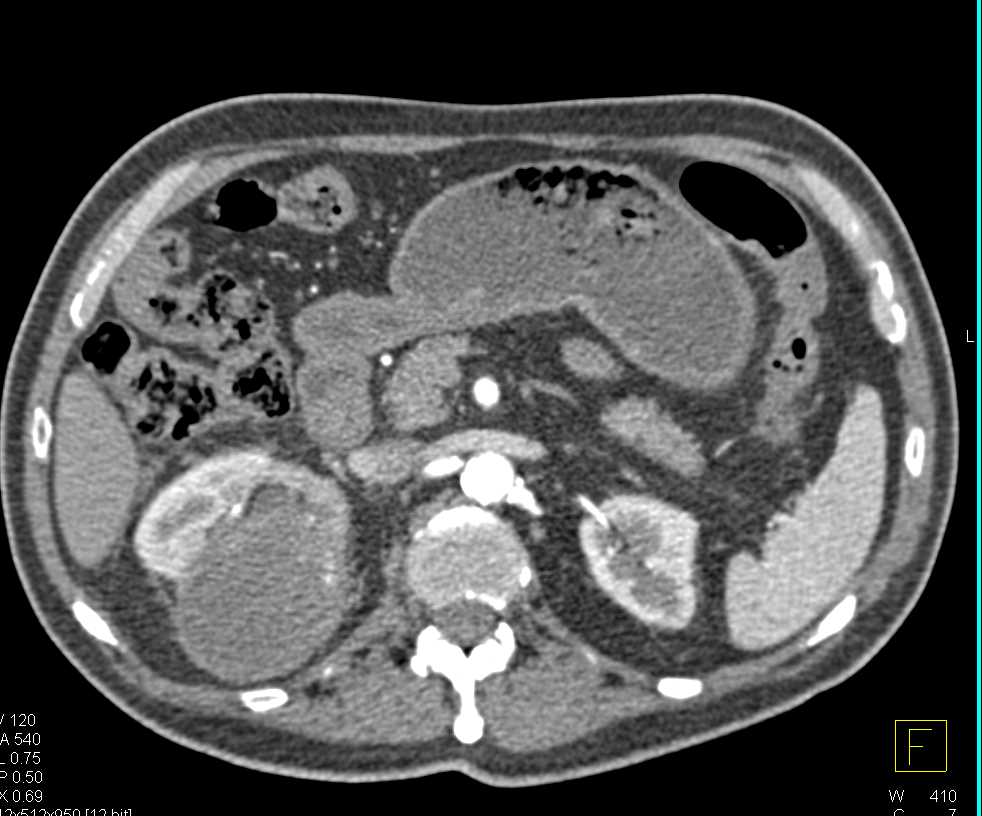

End Stage Renal Disease with Extensive Renal Artery Calcification